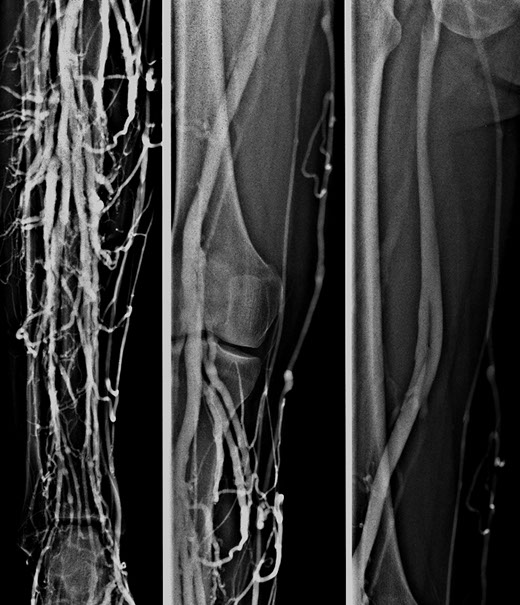

Phlebographie

(Kontrastmittel-Untersuchung der Venen)

Bei der Phlebographie (Untersuchung speziell der Beinvenen) wird ein jodhaltiges Kontrastmittel (KM) zumeist in eine Fußrückenvene eingespritzt. Das KM gelangt langsam über die Unterschenkelvenen in den Oberschenkel, in weiterer Folge in die Beckenetage und ermöglicht eine gute Darstellung all dieser Venen.